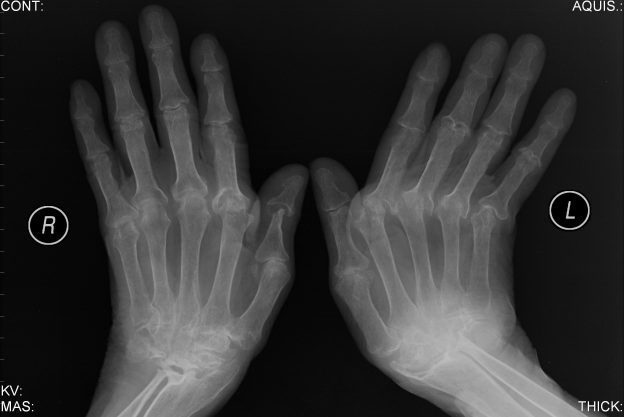

Artrite e artrose são doenças semelhantes, elas têm causas e tratamento diferentes, mas os sintomas podem ser iguais, o que costuma causar alguma confusão. O que as une é um sintoma em comum: dores intensas nas articulações. Consulte um Reumatologista e mantenha bons hábitos de vida, peso adequado e uma alimentação equilibrada.

Reumatologista explica diferença entre artrite e artrose